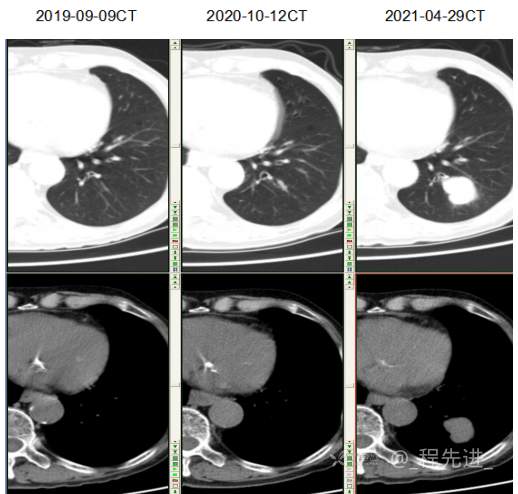

主诉: 反复咳嗽、咳痰10余年,加重10余天

现病史:患者10年前开始出现反复咳嗽、咳痰,3年前出现活动性气喘,休息后症状可缓解;冬春季节或受凉后症状加重,不伴反复下肢浮肿,曾在我院住院诊断为”慢性阻塞性肺疾病”,给予解痉平喘、化痰、输氧治疗有效,平素生活能自理,不能从事体力劳作,此次发病于10天前可能受凉后咳嗽、咳痰加重,咳黄痰,呈阵咳,咳白痰,活动气喘加重,不伴畏寒、发热,无胸痛,今来我院就诊,拟“慢性阻塞性肺病伴急性加重”收住入院,自发病以来,患者精神、食纳、睡眠一般,大小便如常,体重有下降,县体不详。患者及陪护人员:否认14天内离开过南丰,否认14天内有新型冠状病毒感染病例报告社区或中高风险地区的旅行史或居住史,否认14天内与新型冠状病毒感染的患者或无症状感染者有接触史,否认14天内曾接触过来自有病例报告社区或中高风险地区的发热或有呼吸道症状的患者,否认14天内在小范围如家庭、办公室、学校班级等场所,出现5例及以上发热和/或呼吸道症状的聚集性发病病例。